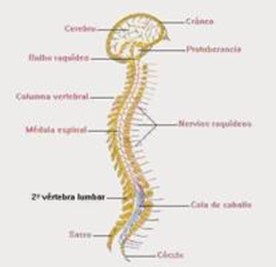

La parte craneal (porción superior o encefálica) de este tubo, presenta dilataciones y, después de una serie de transformaciones, formará el encéfalo. La parte caudal (porción inferior) mantiene su forma tubular y dará lugar a la médula espinal. El tubo neural forma todo lo que son las estructuras de la columna vertebral, contiene al sistema nervioso central.

La médula espinal: Se halla alojada en el conducto raquídeo (el hueco que está en medio de las vértebras de la columna) y está encargada de llevar impulsos nerviosos a través de los nervios raquídeos.

Comunica el cerebro con el cuerpo, mediante dos funciones básicas: recibiendo sensaciones de todo el cuerpo y ordenando al cerebro a realizar determinada acción, llevando estas órdenes o impulsos nerviosos hacia el tronco, cuello y extremidades.

Entre sus funciones también encontramos el control de movimientos no voluntarios.